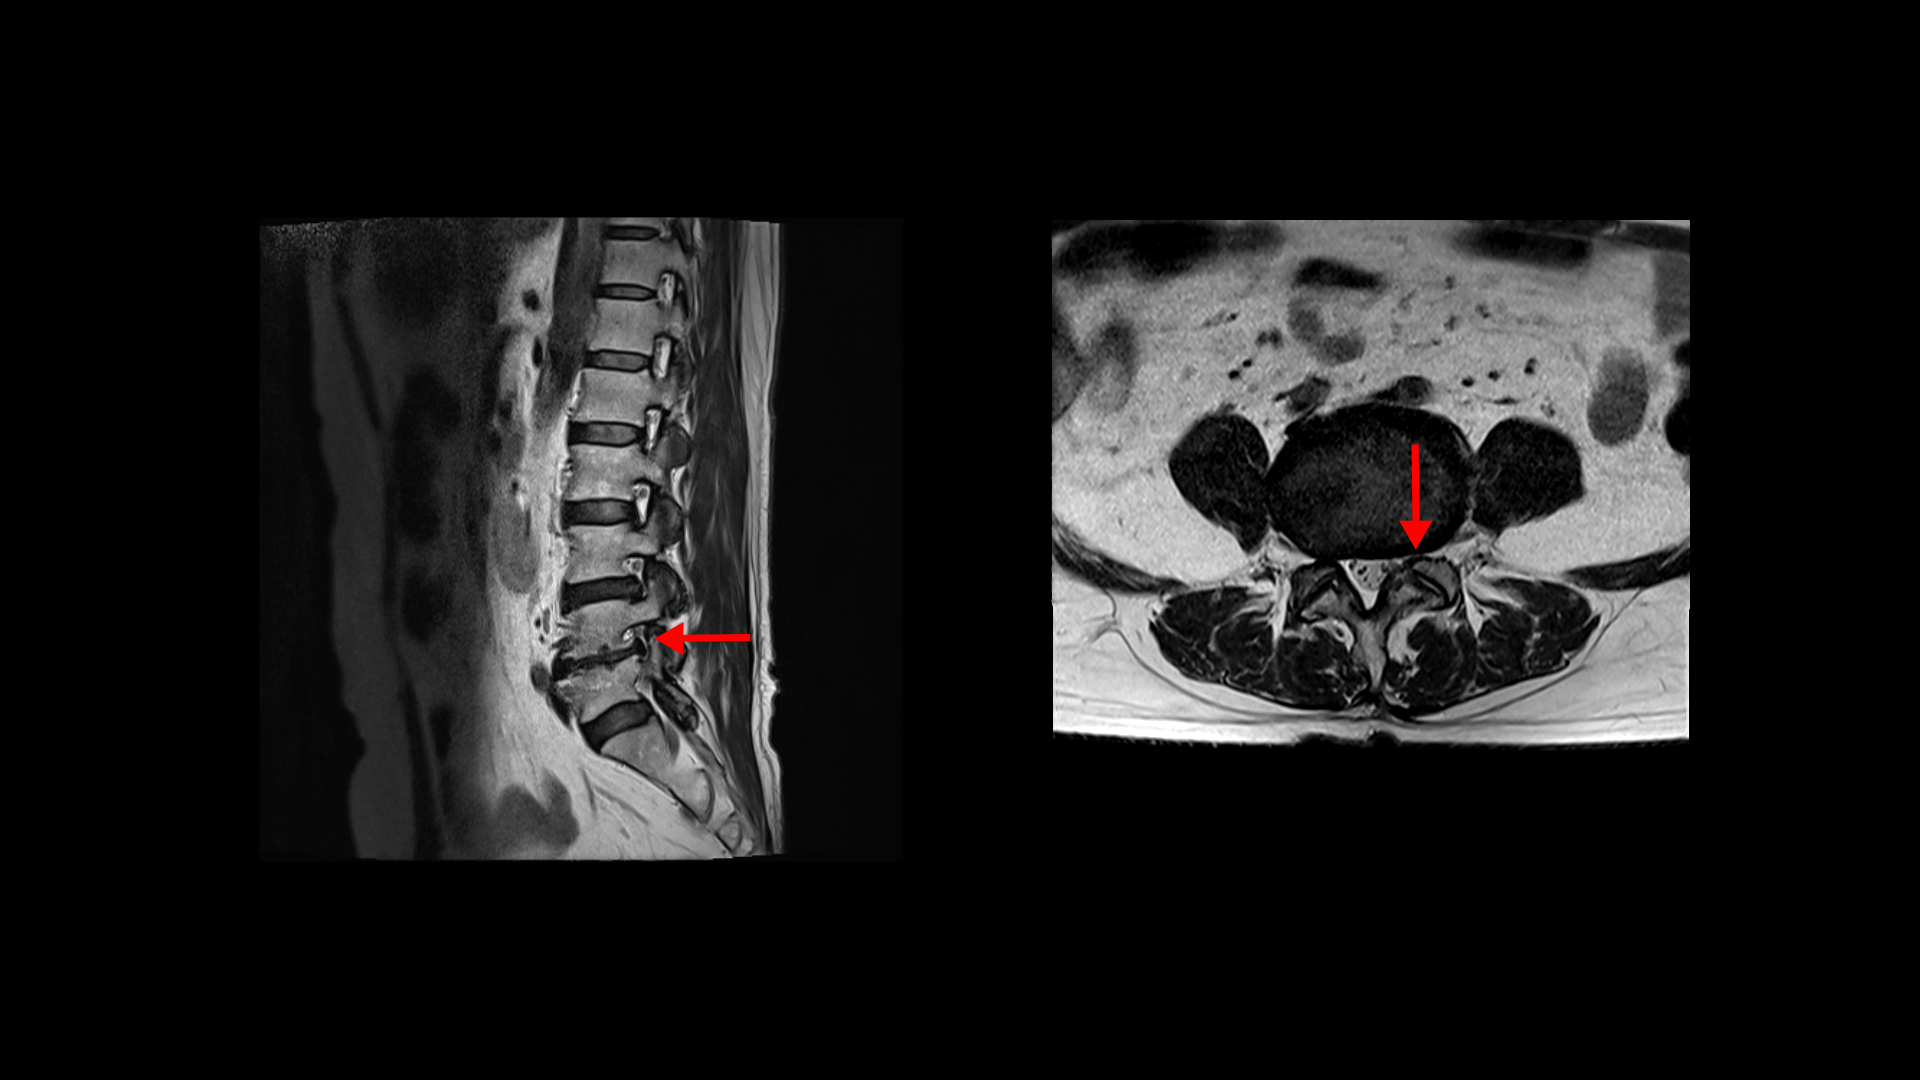

허리MRI를 보면 두 마디의 퇴행성디스크와 추간공협착이 있습니다.

3번 4번은 왼쪽 중앙으로 밀려나와있고

4번 5번은 왼쪽 신경이 빠져나가는 추간공이 뼈가 자라면서 좁아져 추간공협착이 있습니다.